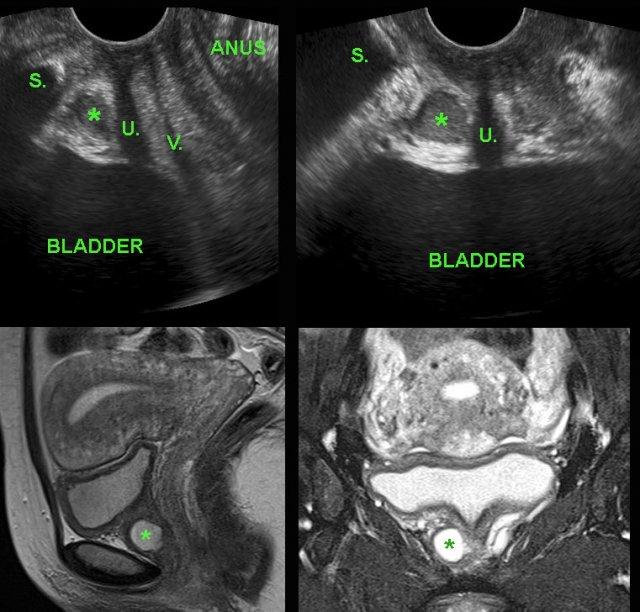

Ung thư bàng quang

Trong quá trình siêu âm đầu dò âm đạo thường quy, bác sĩ phụ khoa phát hiện một khối đặc, tăng sinh mạch máu rõ, bờ tương đối rõ với đường kính 2,5 cm, xuất phát từ thành bàng quang.

Bệnh nhân không có tiền sử đái máu hay rối loạn tiểu tiện.

Phẫu thuật nội soi bàng quang xác nhận ung thư biểu mô tế bào chuyển tiếp độ 1.